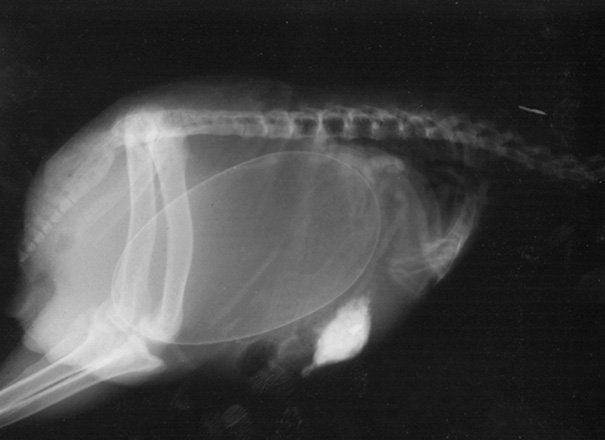

Итак, как выглядят рентгеновские снимки беременных животных:

ещё одна черепаха